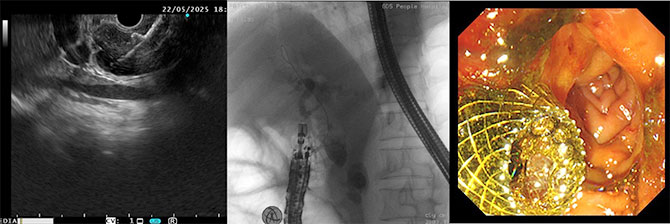

李跃主任医师当即在同台手术中无缝转换技术路径,在肝内胆管扩张不显著的情况下,给患者成功实施了超声内镜引导下胆总管-十二指肠吻合术(EUS-BD-CDS),在扩张的胆总管和十二指肠之间放置了一个支架,使得淤积的胆汁经过支架排向肠道。

手术效果立竿见影!患者堵塞的胆道瞬间通畅,黄疸很快就消退了,胆汁顺利排出,身体指标明显好转,为后续的抗癌治疗争取到了宝贵时间。

省医首例超声内镜下胆总管-十二指肠吻合术